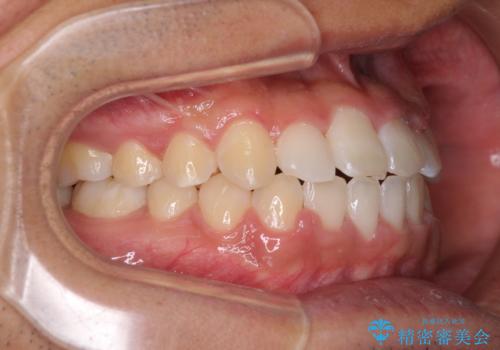

今後はすり減ってしまった歯の形をセラミッククラウンで改善したいとのことで、クロスバイトが改善し咬みやすくなった時点で装置を外すこととしました。

1年で治療を終えることができ、患者様には大変満足していただきました。